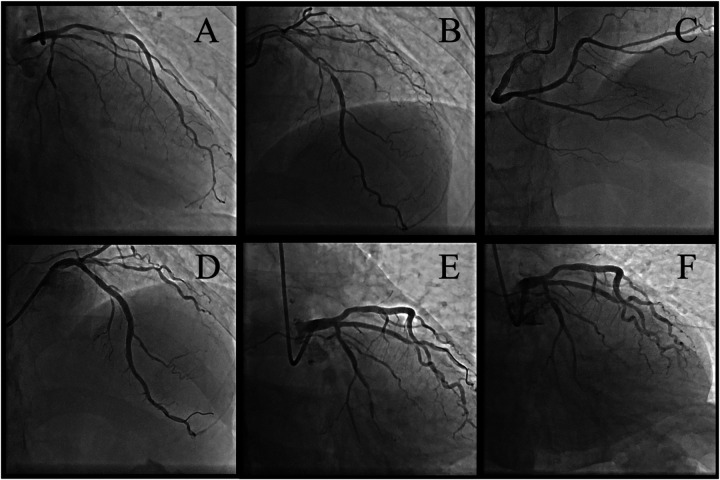

Case summary: A 51-year-old male with immune nephritis, chronic kidney disease (CKD), and poorly controlled hypertension presented with unstable angina. Coronary angiography revealed multivessel disease [70% stenosis in the proximal left anterior descending artery (LAD) and 90% in the posterior descending artery]. Initial treatment included angioplasty with a drug-coated balloon in the posterior descending artery, dual antiplatelet therapy, statins, and prednisone (10 mg/day). Seven months later, after self-reducing GCs to 5 mg/day, he suffered an acute myocardial infarction due to LAD plaque rupture, confirmed by optical coherence tomography (OCT) showing fibrolipid-rich plaques, deep calcifications, and minimal lumen area (0.67 mm2). Emergency stenting was performed to stabilize the patient, with no recurrence at 3-month follow-up.